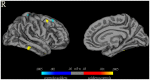

The aim of this study was to investigate brain structural alterations in adult immigrants who adapted to high altitude (HA). Voxel-based morphometry analysis of gray matter (GM) volumes, surface-based analysis of cortical thickness, and Tract-Based Spatial Statistics analysis of white matter fractional anisotropy (FA) based on MRI images were conducted on 16 adults (20-22 years) who immigrated to the Qinghai-Tibet Plateau (2300-4400 m) for 2 years. They had no chronic mountain sickness. Control group consisted of 16 matched sea level subjects. A battery of neuropsychological tests was also conducted. HA immigrants showed significantly decreased GM volumes in the right postcentral gyrus and right superior frontal gyrus, and increased GM volumes in the right middle frontal gyrus, right parahippocampal gyrus, right inferior and middle temporal gyri, bilateral inferior ventral pons, and right cerebellum crus1. While there was some divergence in the left hemisphere, surface-based patterns of GM changes in the right hemisphere resembled those seen for VBM analysis. FA changes were observed in multiple WM tracts. HA immigrants showed significant impairment in pulmonary function, increase in reaction time, and deficit in mental rotation. Parahippocampal and middle frontal GM volumes correlated with vital capacity. Superior frontal GM volume correlated with mental rotation and postcentral GM correlated with reaction time. Paracentral lobule and frontal FA correlated with mental rotation reaction time. There might be structural modifications occurred in the adult immigrants during adaptation to HA. The changes in GM may be related to impaired respiratory function and psychological deficits.